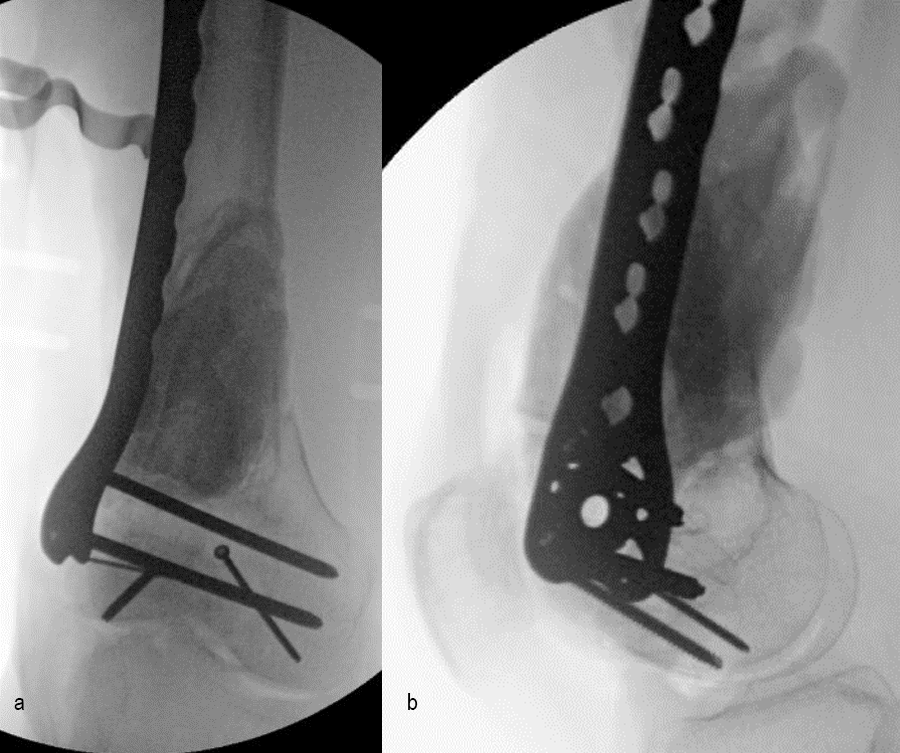

The day following admission, the patient underwent these procedures in the operating room (Fig 6):

> Washout of open injuries right side, including femur and ankle

> Open reduction of the talar injury

> Spanning external fixator of the femur and ankle

> External fixation of the left plafond/talus

At 3 days postoperative, the patient underwent a repeat washout of the right femur and right ankle. The lung injury was still recovering so no definitive fixation was performed at this time.

At 5 days post-initial surgery, the lung injury was improved, so the patient underwent open reduction and internal fixation (ORIF) of the right distal femur with resection of devitalized bone and cement spacer placement (Fig 7). Definitive fixation of the other fractures (ankle and ribs) was undertaken over time.